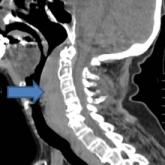

ArticleRetropharyngeal Hematoma in a 90-Year-Old WomanAuthor:Eveline A. Hitti, MDPublish date: September 8, 2017A 90-year-old woman with chronic obstructive pulmonary disease; hypertension; chronic kidney disease; dia...Read More